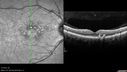

45 year old man was told to come in because of ‘white spots on their retina’. He now has to take his glasses off to read labels. He has always had trouble with oncoming headlights messing up his vision for a short time. VA OD: cc20/20 NscJ1 OS: cc20/20 NscJ1+ Pisciform lesions in the macula of both eyes.

Fundus Flavimaculatus - Asymptomatic - Spectral Domain OCT Line Scan701 views45 year old man was told to come in because of ‘white spots on their retina’.